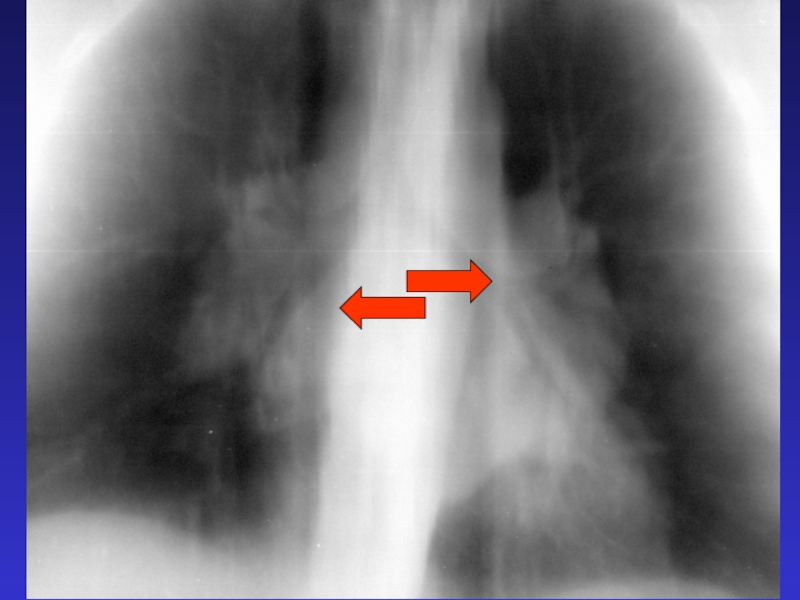

Слайд 83Синдром патологии

корня легкого -

неструктурность и расширение корня легкого

Синдром патологии корня легкого -неструктурность и расширение корня легкого

Слайд 84Причины патологии корня

- увеличение лимфатических узлов - лимфаденопатия

- нарушение

гемодинамики – ЛВГ и ЛАГ

Причины патологии корня - увеличение лимфатических 	узлов - лимфаденопатия- нарушение гемодинамики – 	ЛВГ и ЛАГ

Слайд 88Расширение легочной артерии

Расширение легочной артерии